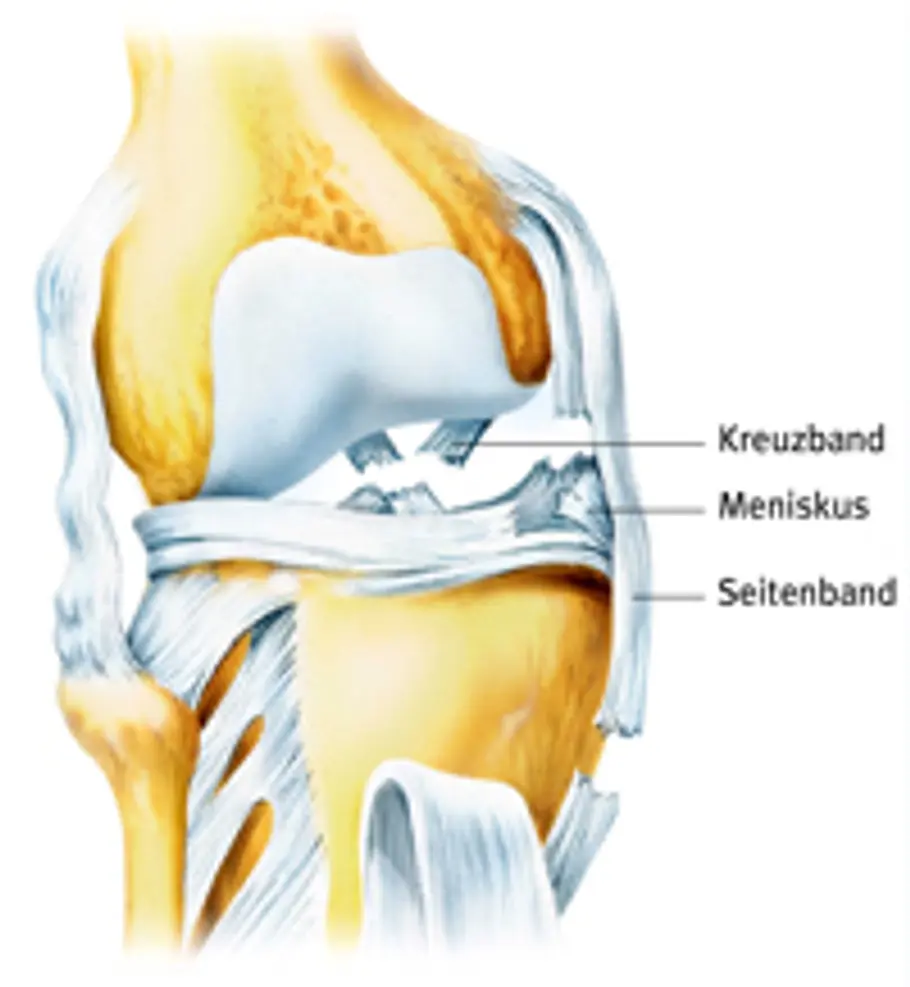

Die beiden Kreuzbänder verlaufen innerhalb des Knies tatsächlich über Kreuz. Sie verbinden die Oberschenkel- mit den Unterschenkelknochen und sorgen so (gemeinsam mit den Seitenbändern) dafür, dass das Knie stabil ist. Dabei trägt das vordere (hier hellere) Kreuzband eine größere Last, als das hintere. Theoretisch kann ein Mensch zwar auch ohne Kreuzbänder laufen und sogar Sport machen. Allerdings werden dadurch die anderen Strukturen im Knie – vor allem Außen- und Innenmeniskus, sowie die Knorpel – so stark belastet, dass sie Schaden nehmen. Es gibt aber sogar Fußballer, die nach einem Kreuzbandriss ohne die stützenden Bänder weiterspielen. So zum Beispiel der Reserve-Keeper von Hannover 96, Markus Miller. In den meisten Fällen werden bei einem Kreuzbandriss auch noch weitere Kniestrukturen, wie Innen- oder Außenband oder Innen- oder Außenmeniskus beschädigt. Eine typische Kombination besteht aus vorderem Kreuzband, Innenmeniskus und Innenband – die sogenannte "Unhappy Triad" (unglücklicher Dreiklang).